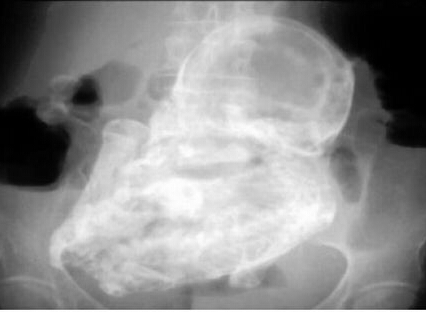

胎儿在82岁老妇体内40年 钙化后形成石胎

426x312 - 51KB - JPEG